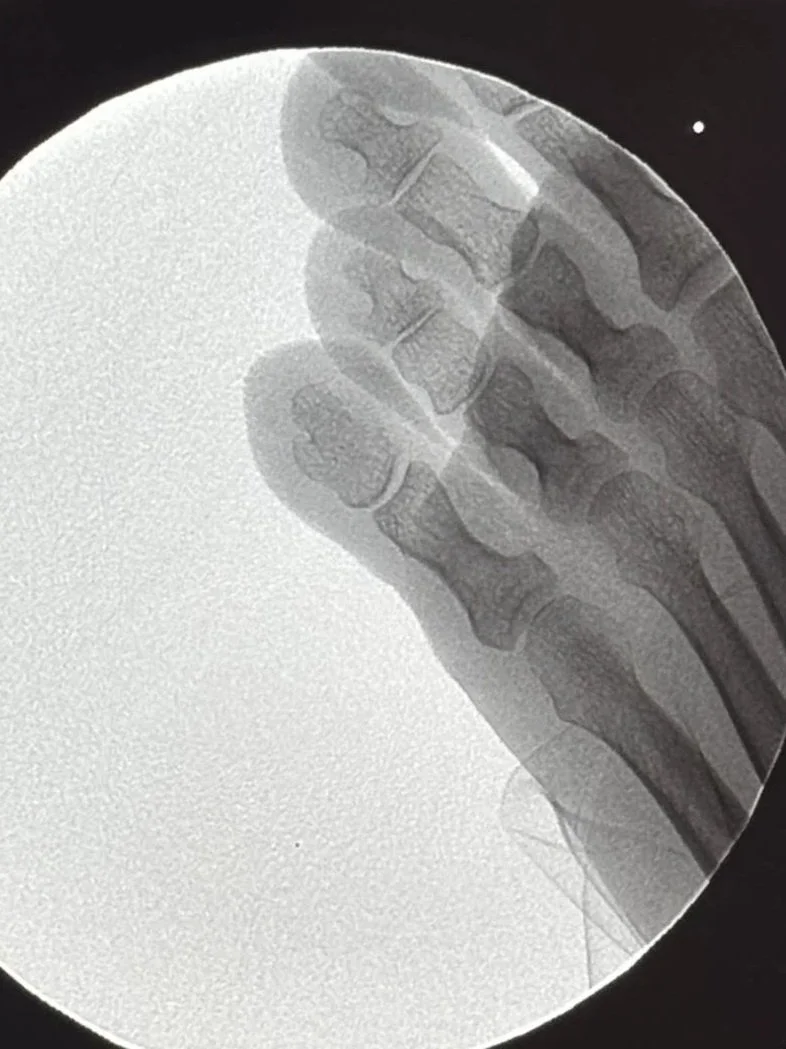

3. Resultado y Recuperación (Post-operatorio)

En la radiografía post-quirúrgica, se observa cómo el relieve óseo ha desaparecido. Al eliminar el factor mecánico (la presión), el heloma no vuelve a salir. La piel recupera su estado natural y el dolor desaparece por completo.